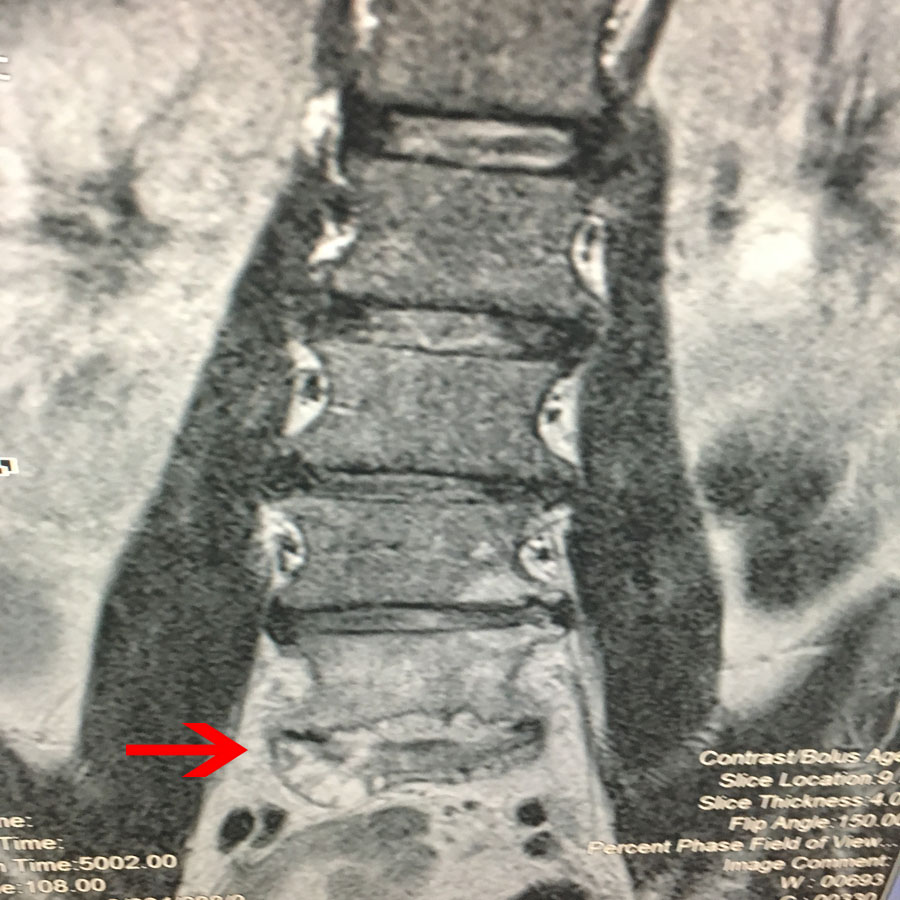

Λόγω επιδείνωσης των συμπτωμάτων το Νοέμβριο του ιδίου έτους εγένετο έλεγχος της Ο.Μ.Σ.Σ. με μαγνητική τομογραφία, η οποία έδειξε παθολογική εξεργασία στο επίπεδο Ο5-Ι1 του 5ου οσφυικού – 1ου ιερού σπονδύλου, και ολόσωμος ραδιοϊσοτοπικός έλεγχος με Τεχνήτιο 99-MDP και γ-κάμερα, 3 φάσεων.

Εικ 1: Προ-εγχειρητική Μαγνητική Τομογραφία ΟΜΣΣ α,β,γ,δ Οβελιαία (Sagittal) λήψη – Ακολουθία Τ1-Τ2 , ε,στ Εγκάρσια (Axial) λήψη – Ακολουθία Τ2

Παρατηρείται έντονη φλεγμονώδης ιστική αντίδραση στο επίπεδο Ο5-Ι1 η οποία αφορά τους σπονδύλους Ο5 και Ι1 και τον μεσοσπονδύλιο δίσκο Ο5-Ι1.